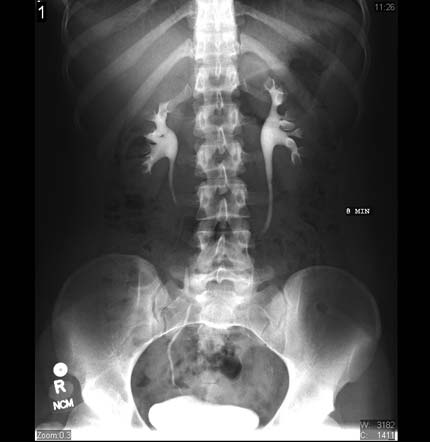

PIV. Se observa contraste en los riñones, uréteres, y en la vejiga.

Nota: Las imágenes se muestra para fines ilustrativos. No trate de sacar conclusiones comparando esta imagen con otras en el sitio. Solamente los radiólogos calificados deben interpretar las imágenes.